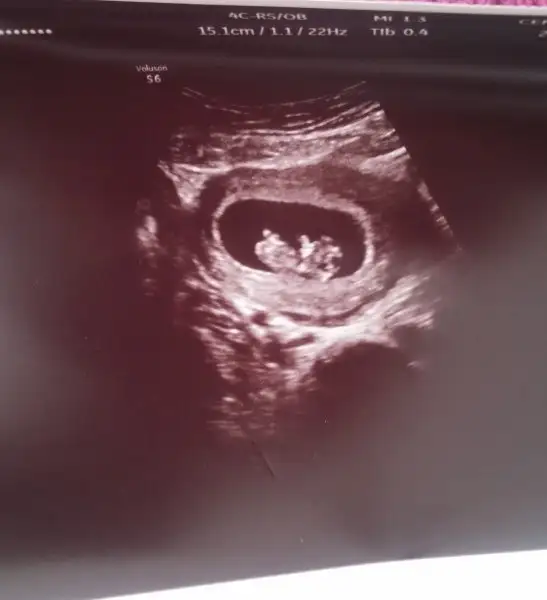

burda nasıl sizce? 8 haftalık bir görüntü

Onu görmedim bebek sağda miYANLIZ BEBEK küçün nokta şeklinde olan diğer halka gibi olan yolk kesesi

bebek ortada :)Onu görmedim bebek sağda mi

doktorumuz dün cinsiyeti söylemiş olsaydı bu teori doğrumu değilmi söyleyebilirdim 16.haftadayım ama miniğim kızmı erkekmi bilmiyorumo zaman bu teoriye göre kız oluyo canım onu bebek sandım ben :)

Canım zaten % 85 ve senin bebek ortada, ne sağ ne sol..doktorumuz dün cinsiyeti söylemiş olsaydı bu teori doğrumu değilmi söyleyebilirdim 16.haftadayım ama miniğim kızmı erkekmi bilmiyorum